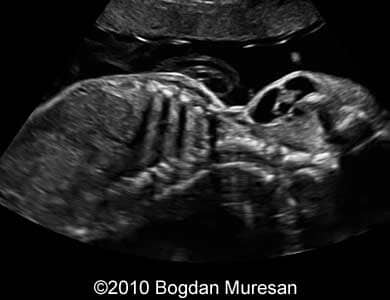

Images 1- 4: 23 weeks, parasagittal view of the cervical region, note multilocular cystic tumor located below the mandible.

Images 7-10: Images of the face of the baby, note the lymphoma deforming the face and submandibular region.